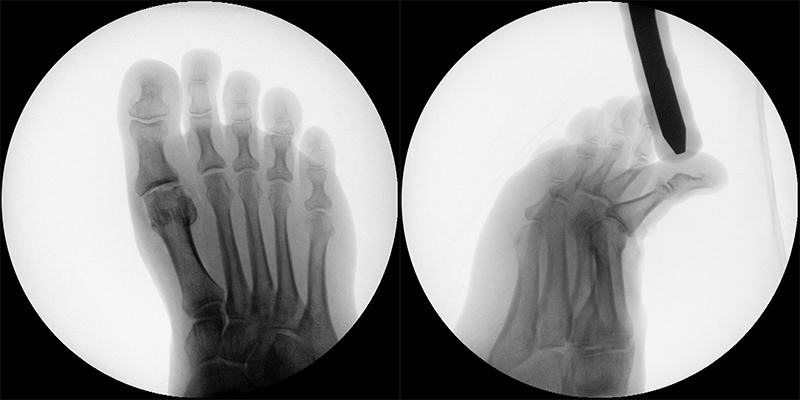

Zum Lesen der Bildbeschreibung und zur Vollansicht bitte das Bild anklicken (Foto: M. Walther).

Zum Lesen der Bildbeschreibung und zur Vollansicht bitte die Bilder anklicken (Fotos: M. Walther).